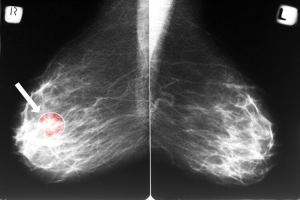

早期乳腺癌症状并不明显,也容易被大众忽视。因此定期筛查尤为重要。建议适龄女性,应每年进行乳腺钼靶(乳腺X线筛查)和B超检查,这也是乳腺癌常用的筛查手段。